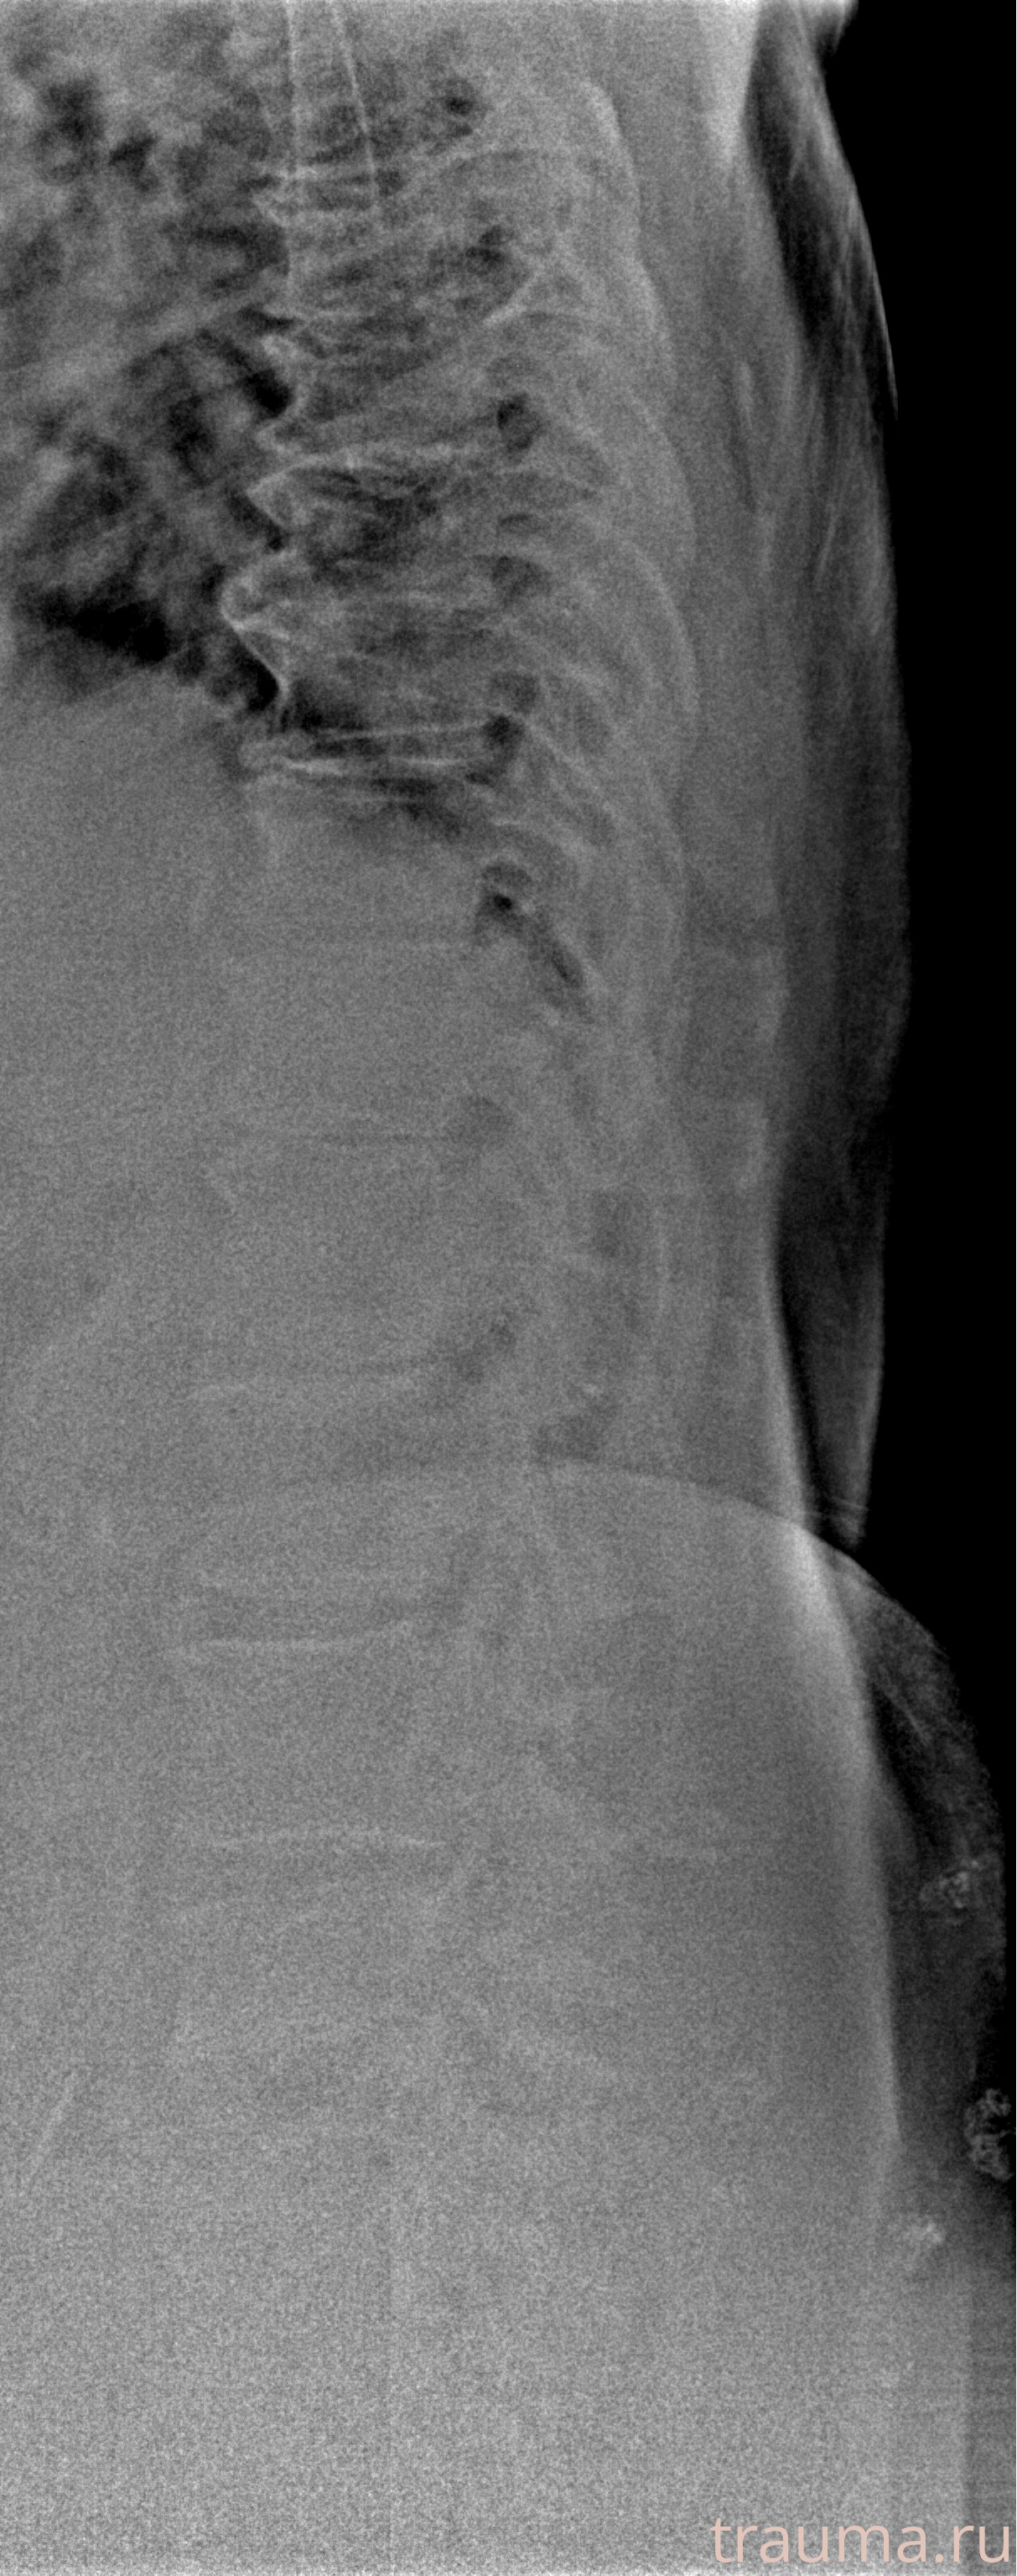

Рентген на дому: по вашему адресу приезжает врач-рентгенолог, травматолог-ортопед с мобильным рентгеновским аппаратом, проводит диагностику травмы или заболевания, делает необходимые рентгенограммы, дает рекомендации по дальнейшему лечению. Получить качественные снимки в домашних условиях возможно благодаря уникальной методике, разработанной МосРентген Центром для института  Склифосовского